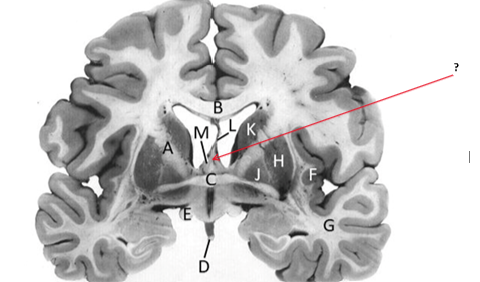

Name this and state its function.

Corpus Callosum.

Putamen.

Name this, state its function, pathways and cellular components.[5 marks]

Caudate nucleus.

Medium spiny neurons utilising GABA and some Cholinergic.

From cortex–>CN–>hippocampus, Gp and thalamus.

Septum pellucidum.

Fornix.

Anterior commissure.

Interconnects:

Infundibular stalk.

Insula.

Name this, state its function, components[2] and the difference in pathways.

Internal capsule.

Anterior limb:

Posterior limb:

Corticospinal tracts and corticopontine tracts: